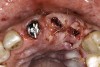

Figure 19  A patient presented requiring extraction of teeth Nos. 8 and 9; note the excellent papilla levels.

Figure 19

Figure 20  Soft-tissue levels were acceptable, but significant bone loss was present.

Figure 20

Figure 21  Eruption was used to attempt to move the bone coronally.

Figure 21

Figure 22  Following the eruption, there was minimal—if any—improvement.

Figure 22

Figure 23  The implants were placed.

Figure 23

Figure 24  Minimal gingival scallop because of the apically placed papilla and a long contact is the expected outcome in a patient with significant interproximal bone loss before implant placement.

Figure 24